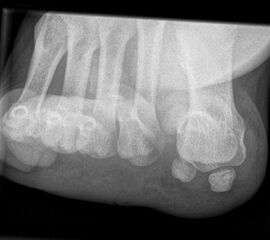

Besondere Bemerkungen zum Beispielbild:

• Verlaufskontrolle nach korrigierendem Vorfußeingriff bei Riesenwuchs des 2. Strahls mit verdicktem Os metatarsale II.

• Z.n. Amputation des Zehenendglieds D2.

• Z.n. Weil Osteotomie des Os metatarsale II.

• Hallux valgus interphalangeus.

• Z.n. Amputation des Zehenendglieds D2